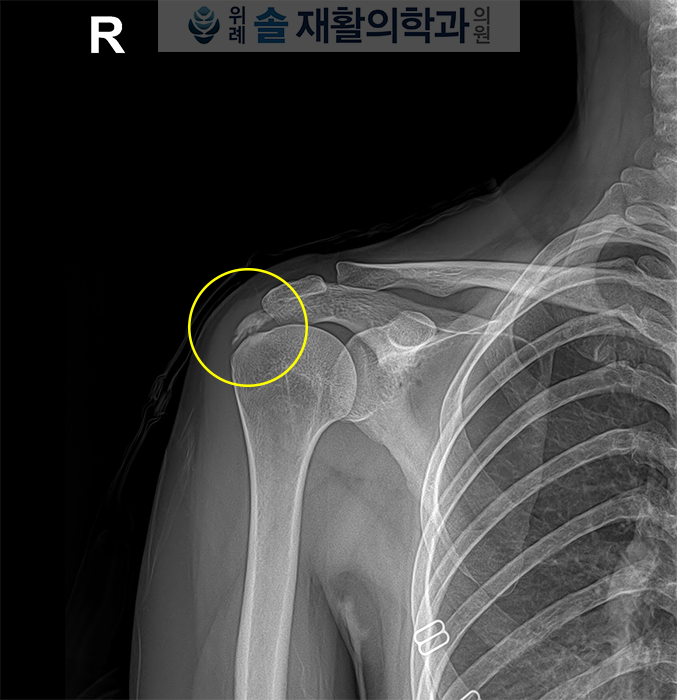

먼저 엑스레이 검사를 시행해보았습니다.

엑스레이 검사상 확연히 보이는 석회성 병변이 확인되었으며, 이어서 초음파 검사도 시행하였습니다.

초음파에서도 2cm 길이의 석회성 병변이 회전근개 극상근에 확인되었으며, 압통 부위와 일치하는 소견이 확인되어 회전근개 극상근의 석회성 건염으로 진단하였습니다.